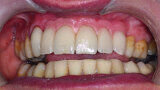

Fig. 30: The patient’s smile showing now well-balanced

incisors in line with the face’s sagittal plane, lip support appearing to be correct.